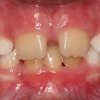

Sügav hambumus või sügav kattumine eesmiste hammaste osas

Normaalse hambumuse puhul katavad ülemised eeshambad alumisi 1/3 krooni pikkuse ulatuses ning alumiste eeshammaste lõikeserv on kontaktis ülemiste lõikehammaste suulaepoolse pinnaga. Sügavhambumuse puhul katavad aga ülemised hambad alumisi lõikehambaid rohkem...